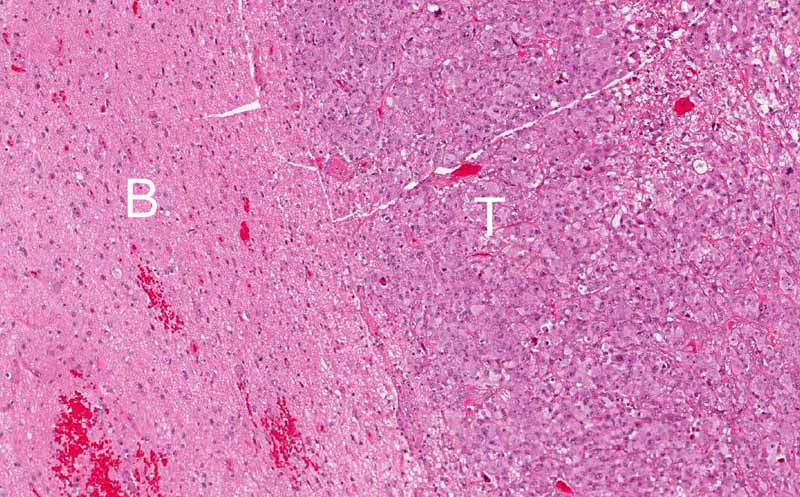

Hematoxylin & eosin

Area 3: The tumor (T) is overall very well demarcated from the surrounding brain tissue (B). This is also an unusual feature of glioblastoma or anaplastic astrocytoma which usually have an infiltrative margin. This features also explain why the tumor appears well demaracted enough to suggest meningioma on imaging studies.

• The periphery of the tumor is rather well demarcated from the surrounding brain tissue (Area 3).